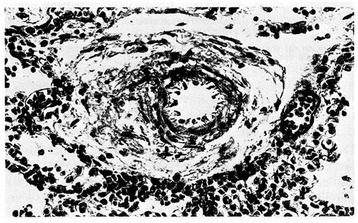

Figure 4.

Pulmonary arterioles from a 22-day-old infant who died from bilateral kidney malformation. Marked thinning of medial muscle mass is evident (PAS-Gieson stains). From Distefano G et al. [12], Med Surg Ped 1992. (Personal observation).